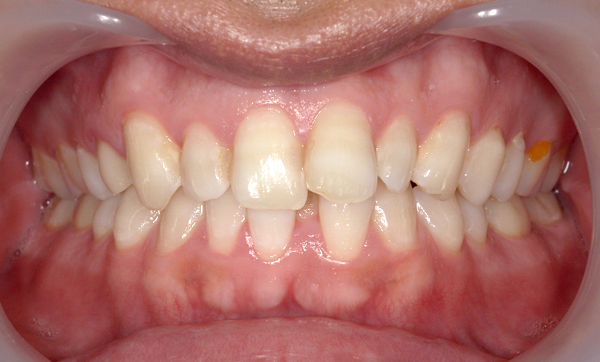

症例_008 「上下の前歯」症例

治療期間:13ヶ月金額:57万円+税40代女性捻転歯前歯のガタガタ

Before | After |

症例_008

治療リスク:後戻りの可能性